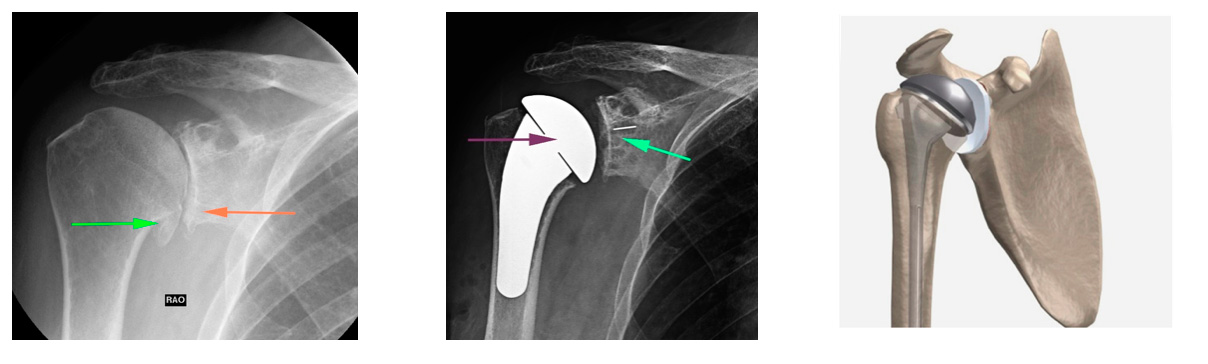

1. Parsiyel Omuz Protezi

Genellikle ileri yaş omuz kırıkları veya sadece humerus başında (topuz) sınırlı kireçlenme olan genç hastalarda tercih edilir. Humerus başı avasküler nekroz (kanlanma bozukluğu) sonucu şekil bozukluğu geliştiğinde de uygulanabilir. Yalnızca topuz kısmı değiştirilir, yuva kısmı korunur.

2. Total Anatomik Omuz Protezi

Omuz ekleminin tamamında kireçlenme (osteoartrit*) olan hastalarda uygulanır. Hem humerus başı hem de glenoid (yuva) yüzeyi değiştirilir. Rotator manşet tendonlarının sağlam olması gerekir; aksi takdirde protezde çıkık veya gevşeme riski artar.

3. Ters Omuz Protezi

Geniş ve onarılamayan rotator manşet yırtıkları, çok parçalı omuz kırıkları veya başarısız protez revizyonlarında kullanılır. Protez, anatomik yapının tersine yerleştirilir: topuz kısmı yuvaya, yuva kısmı topuz haline getirilir. Çıkık riski düşüktür ve ileri yaş hastalarda fonksiyonel sonuçları oldukça iyidir.